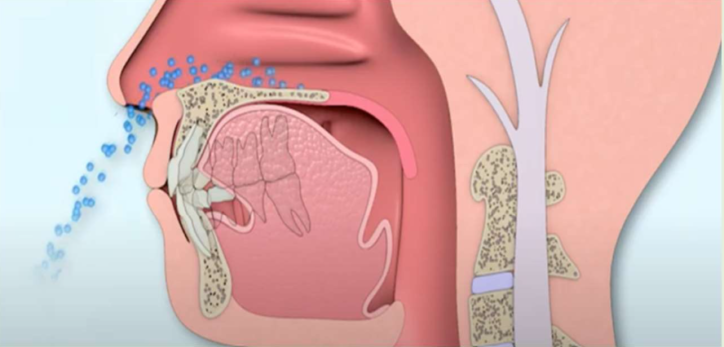

口呼吸と鼻呼吸について

❌ 口呼吸(低位舌)

風邪をひきやすくなる

・細菌やウイルスなどの異物が直接喉に入る

・冷たい乾燥した直接体内に入る

⭕️ 鼻呼吸

免疫力が高まり風邪をひきにくくなる

・ 『鼻毛』がウイルスなどの異物をブロック

・『鼻腔粘膜・扁桃リンパ組織』がさらにブロック

・ 外からの空気の加温・加湿することで乾燥を防止